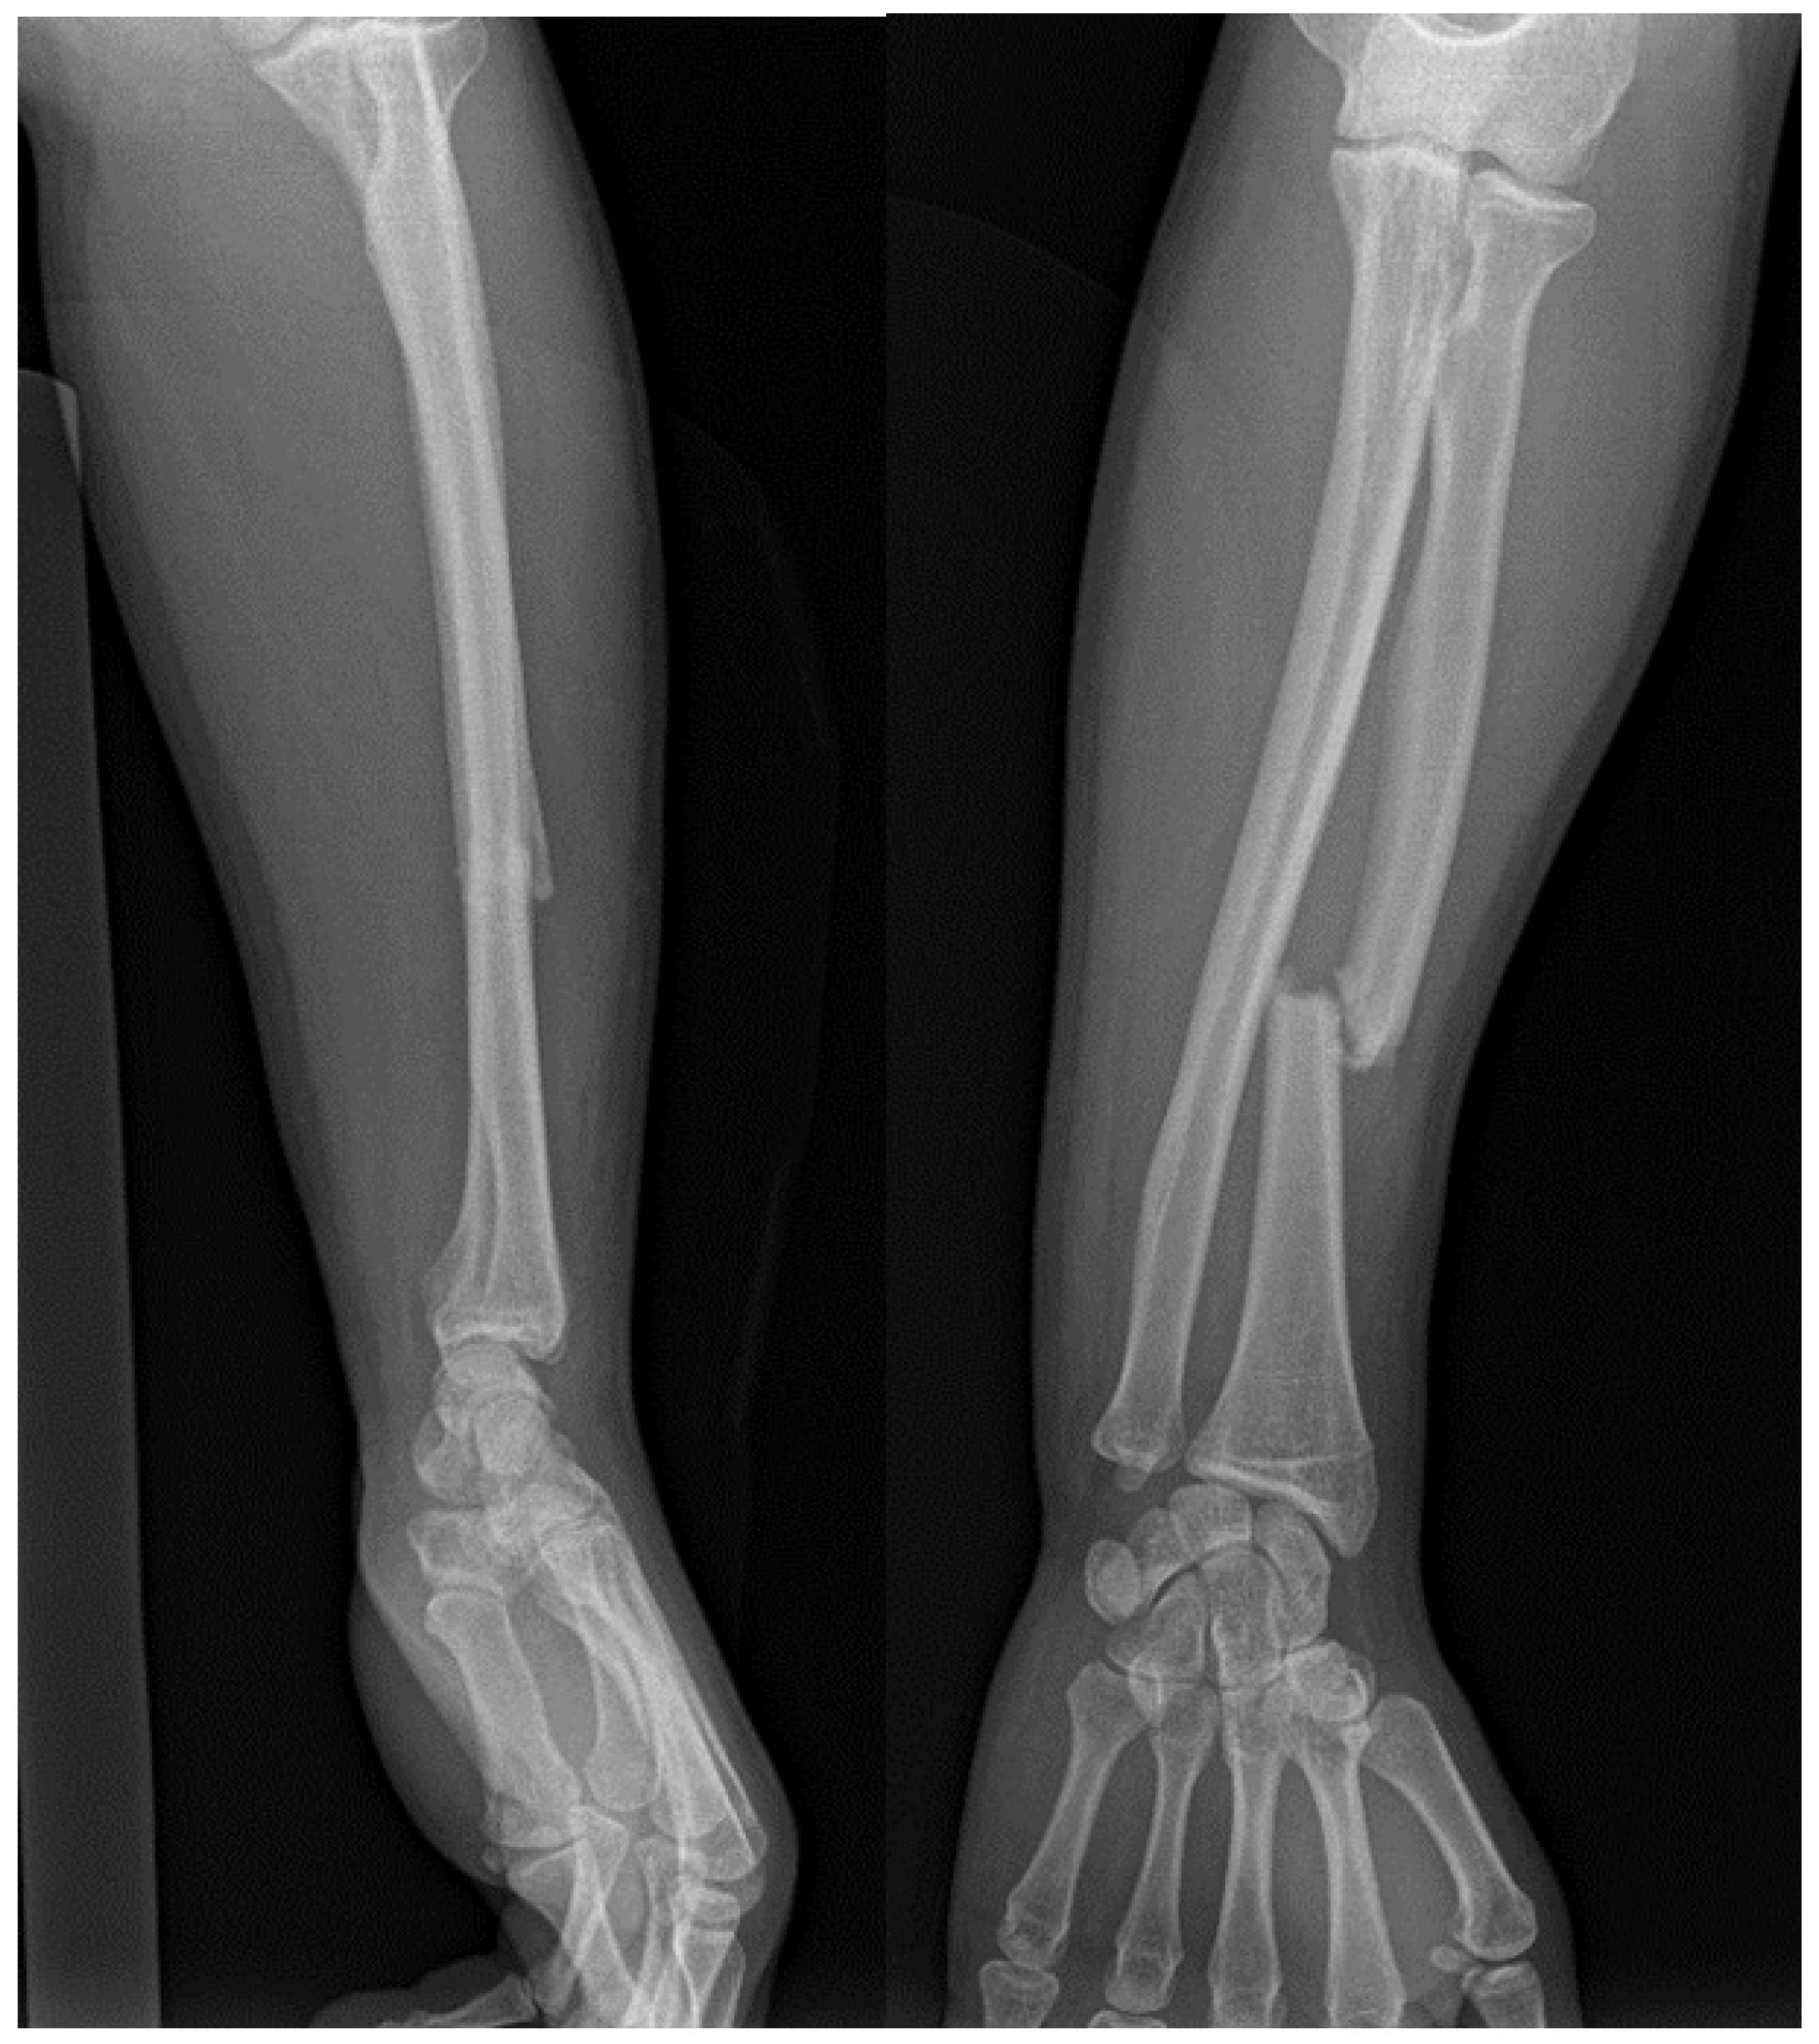

| Galeazzi fractures | High-energy trauma | Clinical presentation: forearm swelling, deformity [60]. Imaging: X-rays, CT scans [7]. | Surgical intervention: ORIF, DRUJ stabilization [7,65,66], postoperative care and rehabilitation. Complications may include persistent pain, stiffness, instability [60]. | Comprises approximately 7% of all forearm fractures [61]. |